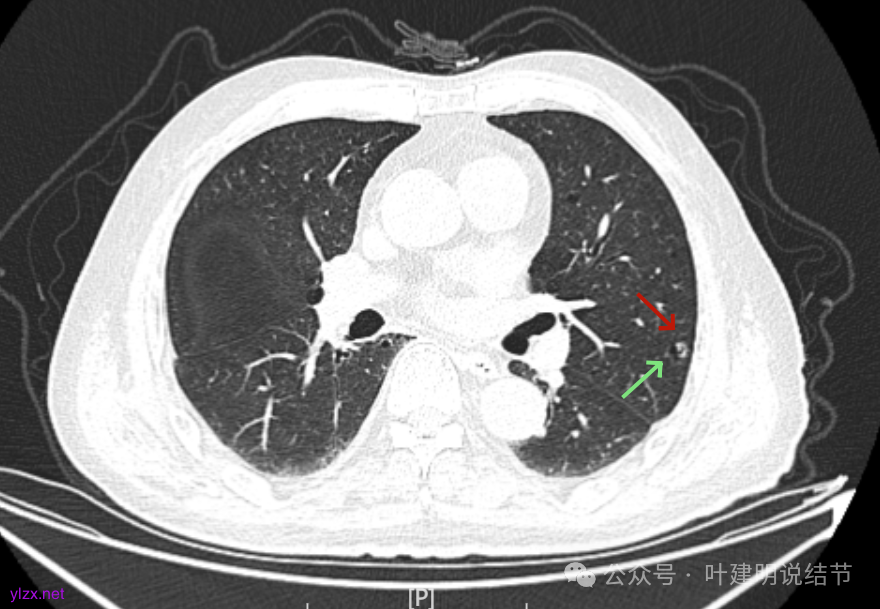

先来看2025年1月的影像:

有囊腔,表面不平,部分囊壁是磨玻璃成分。

病灶囊壁稍不均,多密度较高,表面欠平。

病灶整体的囊壁稍不均,靠内侧有磨玻璃成分。

囊壁不厚但密度较高。

囊腔内壁稍显不光滑,有少许突起于囊腔内。

上图也见囊腔内壁有突起,此层囊壁大部分呈磨玻璃密度。

边缘区是淡磨,内壁少许突起。

左肺上叶红色这处是囊腔型病灶,囊壁略不均,似有微小血管进入囊壁,对比2023年4月整个囊腔来讲有扩大,需要考虑囊腔型肺癌的可能性大。右侧蓝色的并不是典型囊腔型肺癌的表现,再加上两肺绿色这些慢支肺气肿与肺大泡的影像,右侧的就更加不确切,至少近期不能够考虑右侧也要开刀的事情。其实左侧的主病灶相对于其他表现更典型的囊腔型肺癌来说,由于囊壁密度偏高,也不是百分百必定是肺癌。我的想法还是先等脑梗情况稳定,并且间隔4~6个月复查病灶再有进展在考虑单孔胸腔镜下局部切除就可以。淋巴结可以考虑采样,但一般不至于阳性。破是不会切破的。消融不建议,囊腔灶更难通过穿刺获得病理依据,况且东西在边上,能局部楔切,当然首选手术。意见供参考!